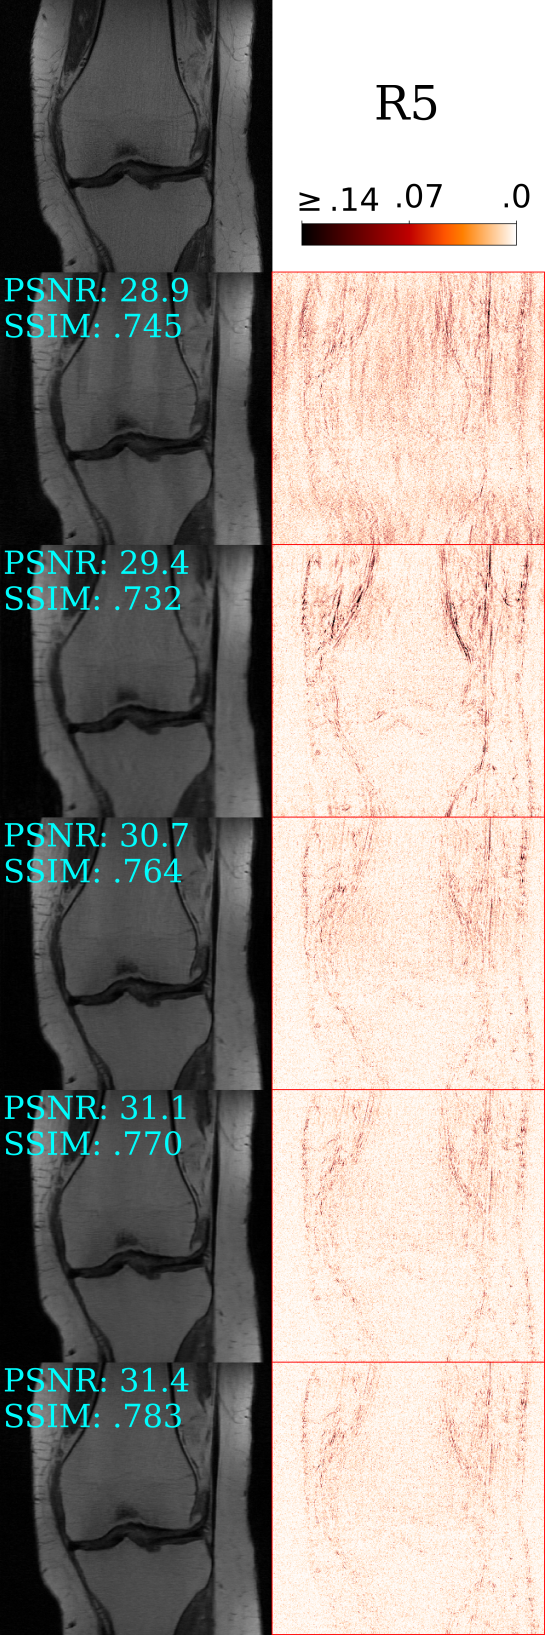

Qualitative Results: Fig. 3 contains a representative comparison between existing single-image techniques D-AMP [2] and ConvDecoder [13] to our proposed approach (best viewed zoomed in). D-AMP does well to remove localised artefacts, however, it struggles with non-local and structured perturbations. ConvDecoder, and to a lesser extent SS, produce localised “ringing” artefacts in the direction of under-sampling. Compared to D-AMP and ConvDecoder, SS effectively penalises non-local and structured CS artefacts, with SS-BM3D scoring higher in terms of PSNR and SSIM (reflected in the error map). Though, SS-BM3D does not meaningfully dampen ringing artefacts as they are not necessarily noise-like. We find SS-D-AMP features the sharpest images with less visible artefacts and better preserved textures, effectively combining the strengths of D-AMP and SS.

Table 2 contains the average performance achieved on the 70 brain and 70 knee test slices. SS-D-AMP scores highest overall, improving upon D-AMP by an average 4.49dB and 2.63dB for brains and knees respectively. The main penalty to SS-D-AMP is the increased computation compared to D-AMP and SS. However, Fig. 4 indicates that the SS-D-AMP estimate at epoch would produce an image with superior image quality compared to SS or SS-BM3D, enabling a reduction in run-time. Further, SS-BM3D’s non-adaptive Gaussian denoising is less efficient at dampening CS-MRI artefacts than SS-D-AMP, requiring more computation time overall. As ConvDecoder is limited to the mapping of a random vector to known measurements , the reconstruction sees some overfitting and scores lowest on the brains.

| Knees | |||||||||

| Zero-Fill | 27.74 | 0.778 | 27.00 | 0.719 | 27.87 | 0.706 | 26.34 | 0.658 | - |

| D-AMP | 30.53 | 0.849 | 30.07 | 0.804 | 30.60 | 0.781 | 29.29 | 0.746 | 78 |

| ConvDec | 33.15 | 0.860 | 31.53 | 0.798 | 30.92 | 0.760 | 29.71 | 0.724 | \ul190 |

| SS | 34.51 | 0.880 | 32.74 | 0.821 | 31.74 | 0.777 | 30.93 | 0.748 | 232 |

| SS-BM3D | \ul 34.52 | \ul 0.881 | \ul 32.79 | \ul 0.822 | \ul 31.79 | \ul 0.778 | \ul 31.02 | \ul 0.750 | 300 |

| SS-D-AMP | 34.65 | 0.884 | 32.97 | 0.829 | 32.04 | 0.792 | 31.33 | 0.767 | 254 |